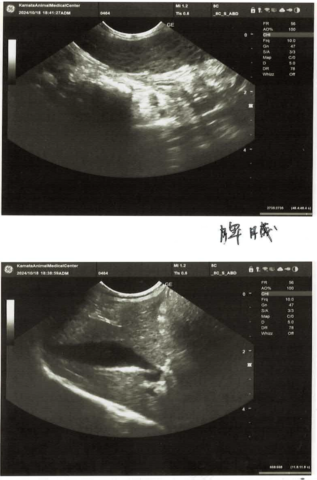

この猫ちゃんは体重減少や下痢や嘔吐の消化器疾患がもあり、血液検査とエコー検査を行いました。

血液検査でもエコー検査でもリンパ腫が疑わしい結果だったため、リンパ節に直接針を刺し細胞をとって検査に出しました。